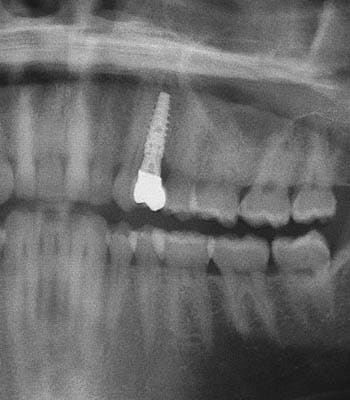

Dental implants are a titanium "root" which can be placed into the jawbone. Once integrated with your bone, the implant can be used to support a crown, a bridge, or secure a complete denture. Dental implants may be used to eliminate partial plates and dentures. The success rates for dental implants are extremely high which is due in part to the fact that root-form implants are made of a biocompatible material, titanium.

Below are a few examples of what DENTAL IMPLANTS can do for you and your smile!

Single Tooth Replacement